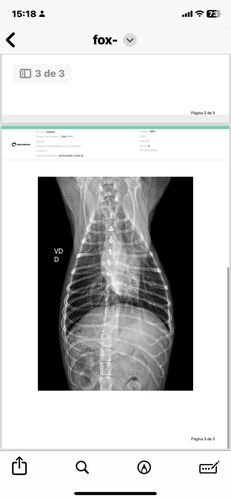

No dia 02 de março de 2025, Fox sofreu um grave acidente. Uma linha de pipa com cerol passou pela laje de casa e cortou a Fox. Assustada, ela caiu da laje de uma altura de 3 metros, sofrendo diversas fraturas nas patinhas e costelas, lesões internas que prejudicaram sua mobilidade.